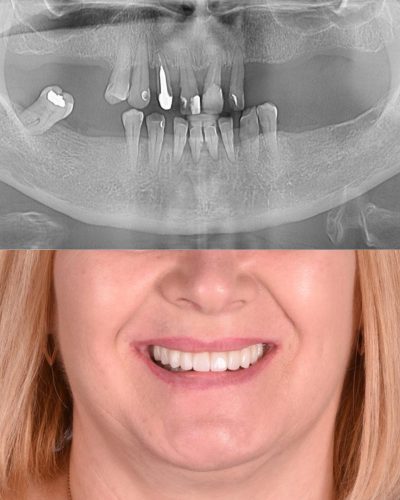

Pacienta s-a prezentat în clinica noastră cu un tablou clinic sever de parodontoză avansată, având un număr foarte redus de dinți restanți (15 dinți), toți cu mobilitate accentuată, pierdere osoasă semnificativă și prognostic nefavorabil.

Diagnosticul inițial

Evaluarea clinică și imagistică a evidențiat:

Menținerea dinților restanți nu reprezenta o soluție viabilă pe termen lung

După analiză multidisciplinară și planificare digitală, s-a stabilit un plan de tratament predictibil și modern, axat pe reabilitare orală totală fixă pe implanturi